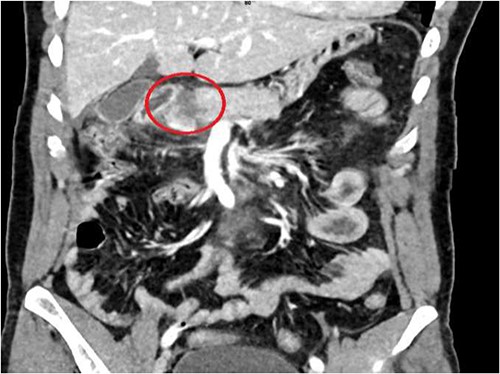

A 36-year-old male manual laborer was assaulted by his roommates (kicked in the abdomen multiple times) and was intoxicated with alcohol. He was writhing in pain, hemodynamically stable with a guarding abdomen. Initial laboratory results showed high serum amylase level 485 U/L, high serum lipase 1200 U/L and elevated liver enzymes. A computed tomography (CT) scan revealed an enlarged bulky head of the pancreas with complete transection of the pancreatic neck (Figs 1–2). In addition, he had a small contusion of the liver and free fluid in the abdomen.

CT abdomen—sagittal section, showing transection of the pancreas (circle).